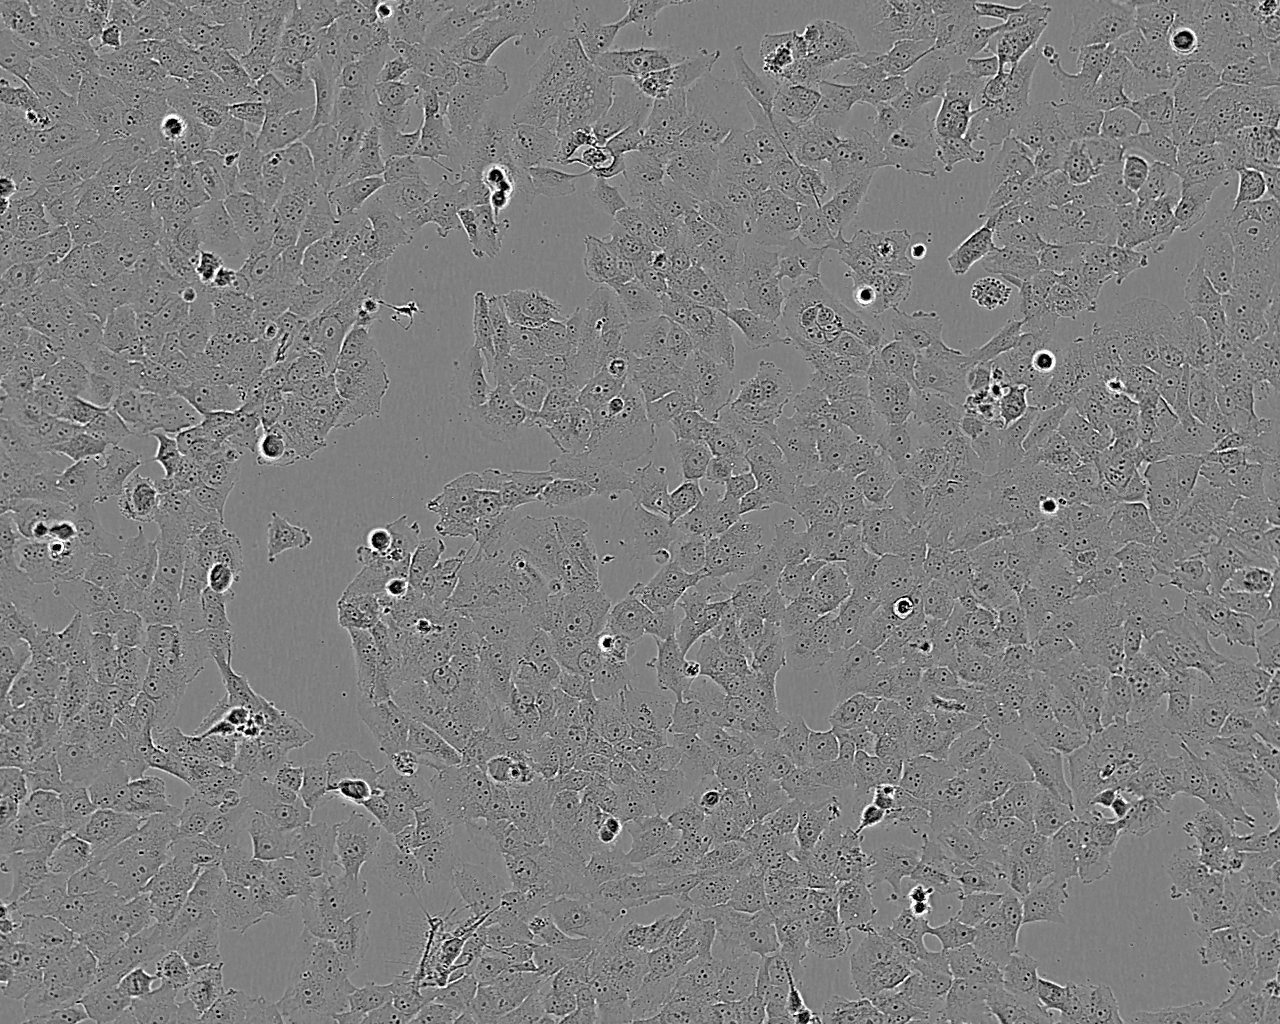

HUVEC-C[HUVEC] 人脐静脉血管内皮细胞系

HUVEC-C[HUVEC]

1x10(6)viable cells/ml